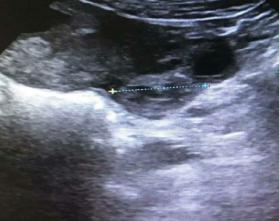

2020年11月9日上午,妇科门诊走进来一位年轻的患者,吴XX,停经2月余,间断少量阴道流血20余天,因阴道流血增多伴左下腹痛来就诊,查B超示:早孕,宫腔积血,左附件区不均质回声(51*37*46mm),盆腔积液。血HCG 125417.00MIU/mL ,孕酮 30.20ng/mL。医生详细询问病史,患者系今年备孕半年未孕,于9月中旬外院促排卵治疗。

这两种可能性都随时可能危及大出血危及患者生命,影响宫内妊娠发育,遂立即予以妇科住院保胎治疗,并密切观察患者生命体征。11.10上午吴女士再次出现持续剧烈左下腹痛,复查B超示:早孕,宫腔积血,左附件区不均质回声(64*49*40mm),盆腔积液。包块较入院明显增大,患者疼痛感明显加重,考虑盆腔存在持续出血,需立即行腹腔镜探查术。医生在向患者及家属交代病情及风险后,急诊在全麻下行腹腔镜探查,术中见盆腔积血约300ml,左侧输卵管壶腹部及伞端增粗约3*4cm,伞端有活动性出血,术中再次医患沟通后行左侧输卵管大部分切除术。剖视标本见机化绒毛组织。术后继续予以药物保胎等对症治疗。

术后病理回示:左侧输卵管妊娠。11.13复查B超:宫腔内扫见49*33*48妊娠囊,其内见卵黄囊及胚芽,有心管搏动,头臀长37mm,提示:早孕。患者无腹痛及阴道流血,11.17再次复查B超无异常后,吴女士终于露出了开心的笑容,与家人愉快的办理了出院。